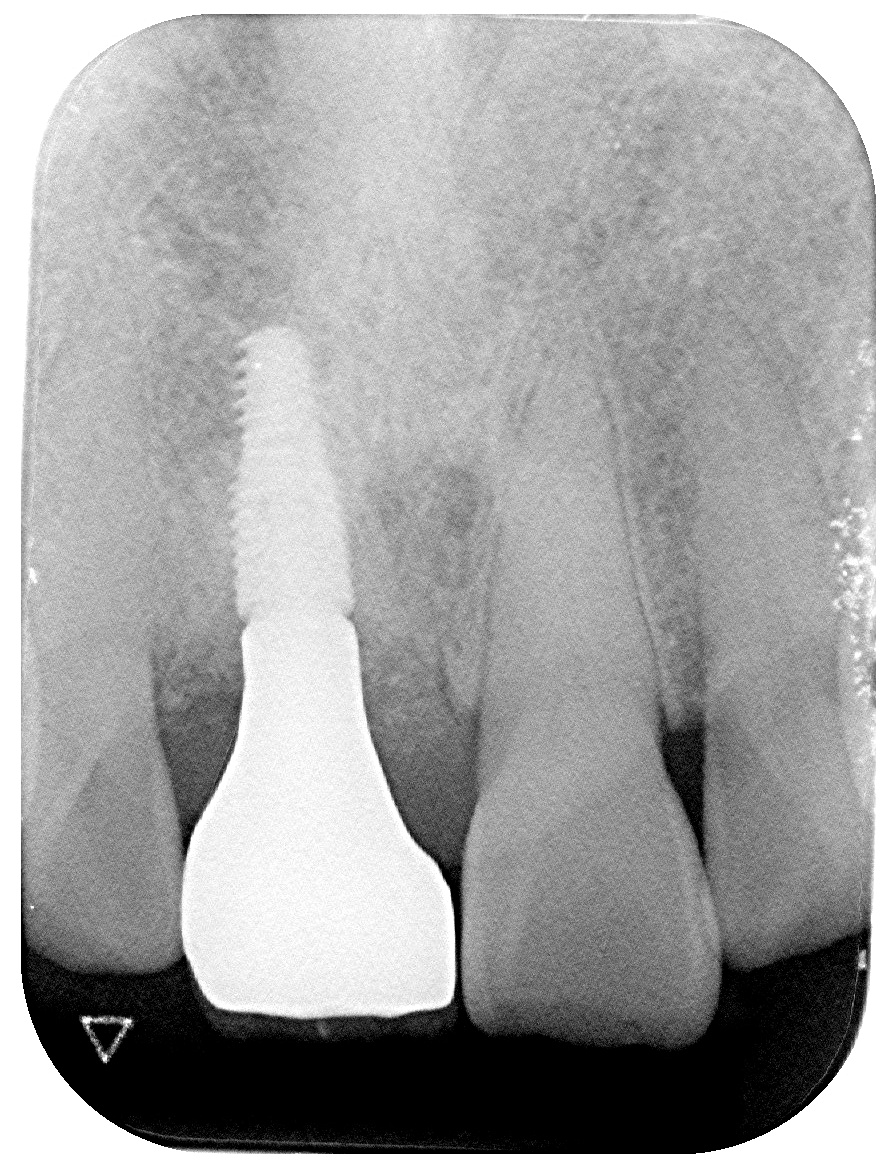

CT撮影を行うと、割れ目が歯根の深い部分まで達していることが分かりました。

このようなケースでは、差し歯(クラウン)などの保存的治療では改善が難しく、

抜歯を前提とした治療計画が必要になります。

抜歯即時インプラント治療を行いました。

抜歯と同時にインプラントを埋入することで、

骨の吸収を最小限に抑えながら見た目と機能を早期に回復できます。